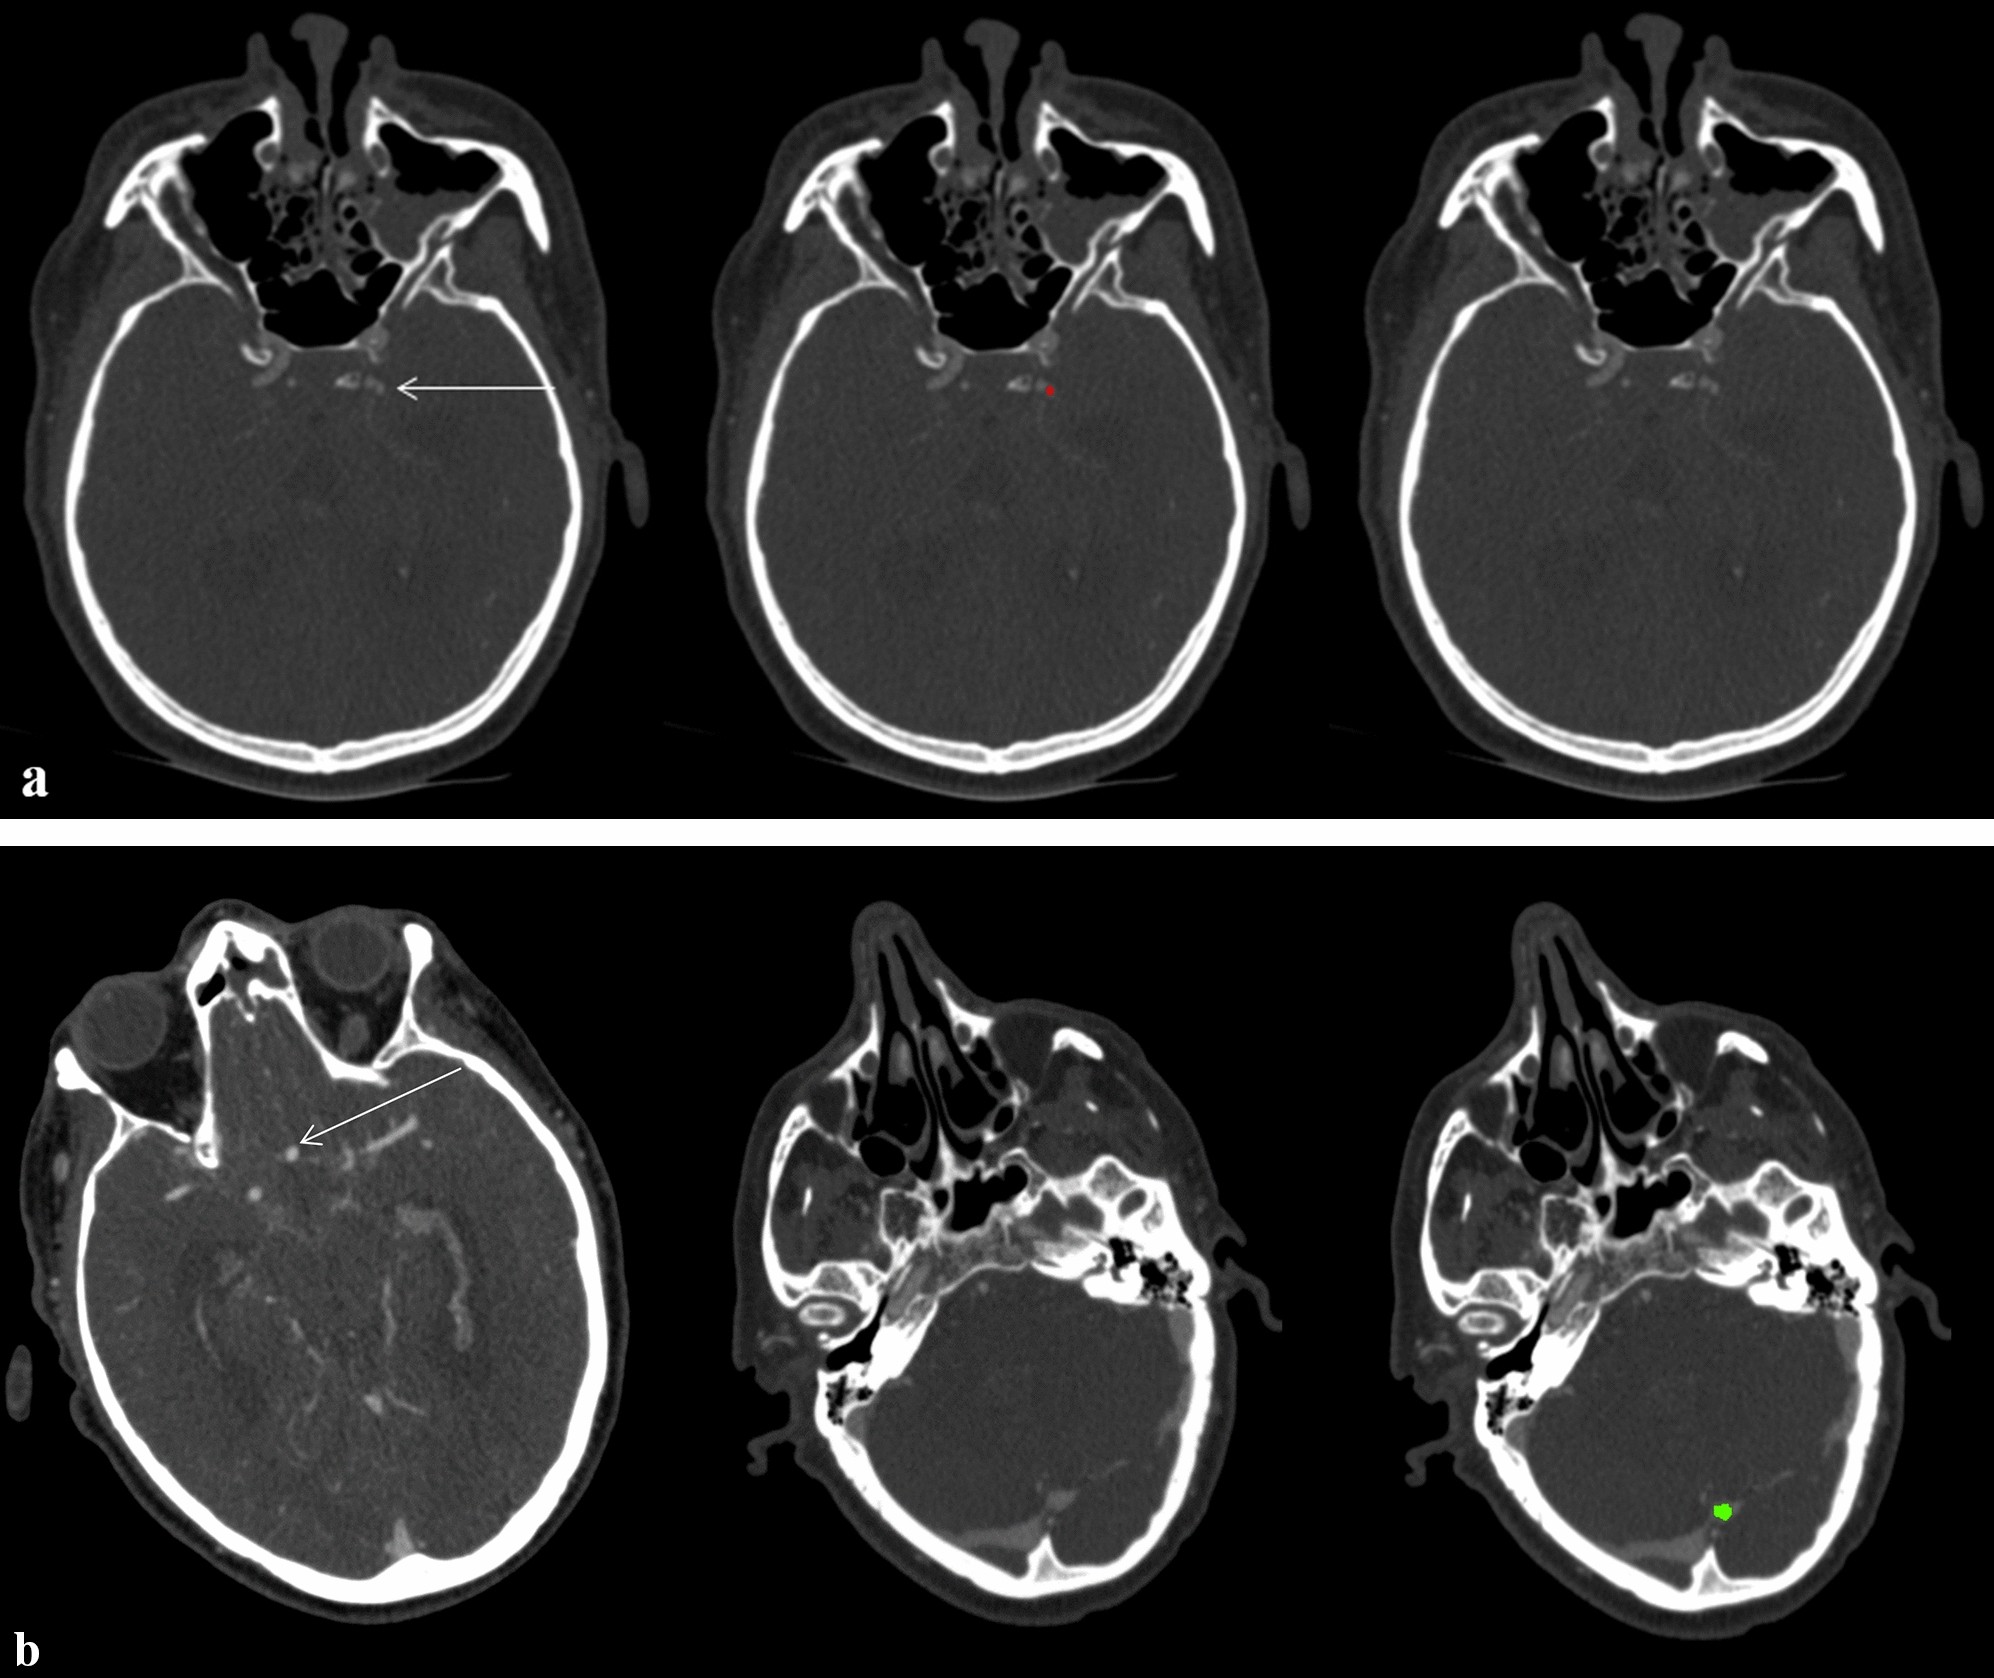

Figure 6

(a) Axial CTA

source images of a 64-year-old male with a small aneurysm (volume based on manual segmentation: 21.8 mm3) of the left internal carotid artery (arrow, red: manual segmentations) being missed by the DLM-Ens. (b) Axial CTA source images of a 65-year-old male with an anterior communicating artery aneurysm (arrow), which was accurately segmented and detected by the DLM. However, a false positive finding of the DLM-Ens (in green) at the superior sagittal sinus/transverse sinus was detected.